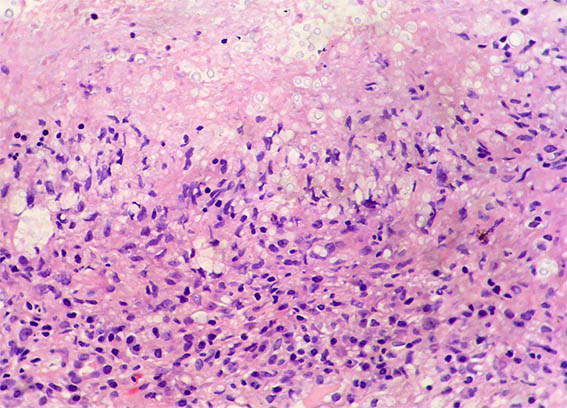

The patient is a 42-year-old man with acute kidney injury of unclear aetiology, creatinine 3.5 mg/dL, BUN: 54 mg/dL; edema in lower limbs, one week of evolution. He does not report other symptoms. As relevant history, the patient was diagnosed with HIV infection 20 days earlier and started antiretroviral therapy 2 weeks ago, which raises the possibility of acute tubulointerstitial nephritis secondary to drugs.

Look at the images of the renal biopsy:

Figure 2. H&E, X200.